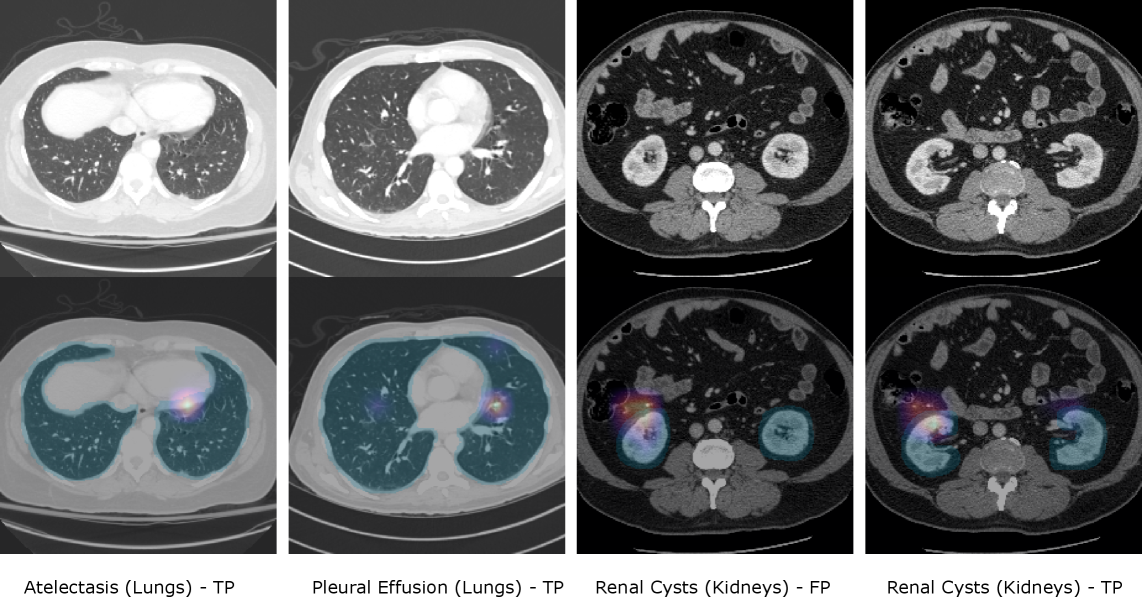

We visualize organ-masked attention for four MERLIN studies using DINOv3 in masked attention mode in Figure 3. Each column shows an axial CT slice (top) and an overlay (bottom) with the organ mask (cyan) and the masked-attention heatmap (magma). For lung findings (atelectasis, pleural effusion), attention remains within the lungs. For renal cysts, the TP example shows kidney-confined evidence; the FP example also shows kidney-confined attention but an incorrect positive prediction. These maps depict organ-level pooling weights used to form the study-level logits—they provide anatomical context for where the model drew evidence, not pixel-accurate lesion segmentations or guarantees of correctness.

Figure 3: Qualitative organ–masked attention on MERLIN. Columns show four study examples: Atelectasis (TP), Pleural effusion (TP), Renal cyst (FP), and Renal cyst (TP). Top row: axial CT slice. Bottom row: organ mask (cyan) with masked–attention heatmap (magma). Maps depict organ-level pooling weights used for study-level classification (not lesion segmentation): they highlight where evidence within the organ contributed most to the logit. The FP renal-cyst case illustrates organ-faithful but misleading evidence.